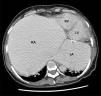

A 55-year-old woman arrived at the emergency room with dyspnea and generalized edema. The patient had as relevant medical history, a mechanical mitral valve, severe tricuspid regurgitation, pericardiectomy apparently due to recurrent pericardial effusion, atrial fibrillation and a pacemaker for complete atrioventricular block. Physical examination revealed signs of right-sided heart failure and tricuspid regurgitation. The chest X-ray (Figure 1), echocardiography and computed tomography (Figure 2) revealed a giant right atrium (18 cm×15.3 cm×16.3 cm) and giant left atrium (13.1 cm×9.6 cm×9.1 cm). Right and left ventricles had normal size and function. She also had severe tricuspid regurgitation and a normally functioning mitral prosthesis. The atria were so large that they were causing pulmonary restriction and dyspnea that was difficult to manage. The patient presented progressive deterioration during hospitalization and despite heart failure treatment she died.